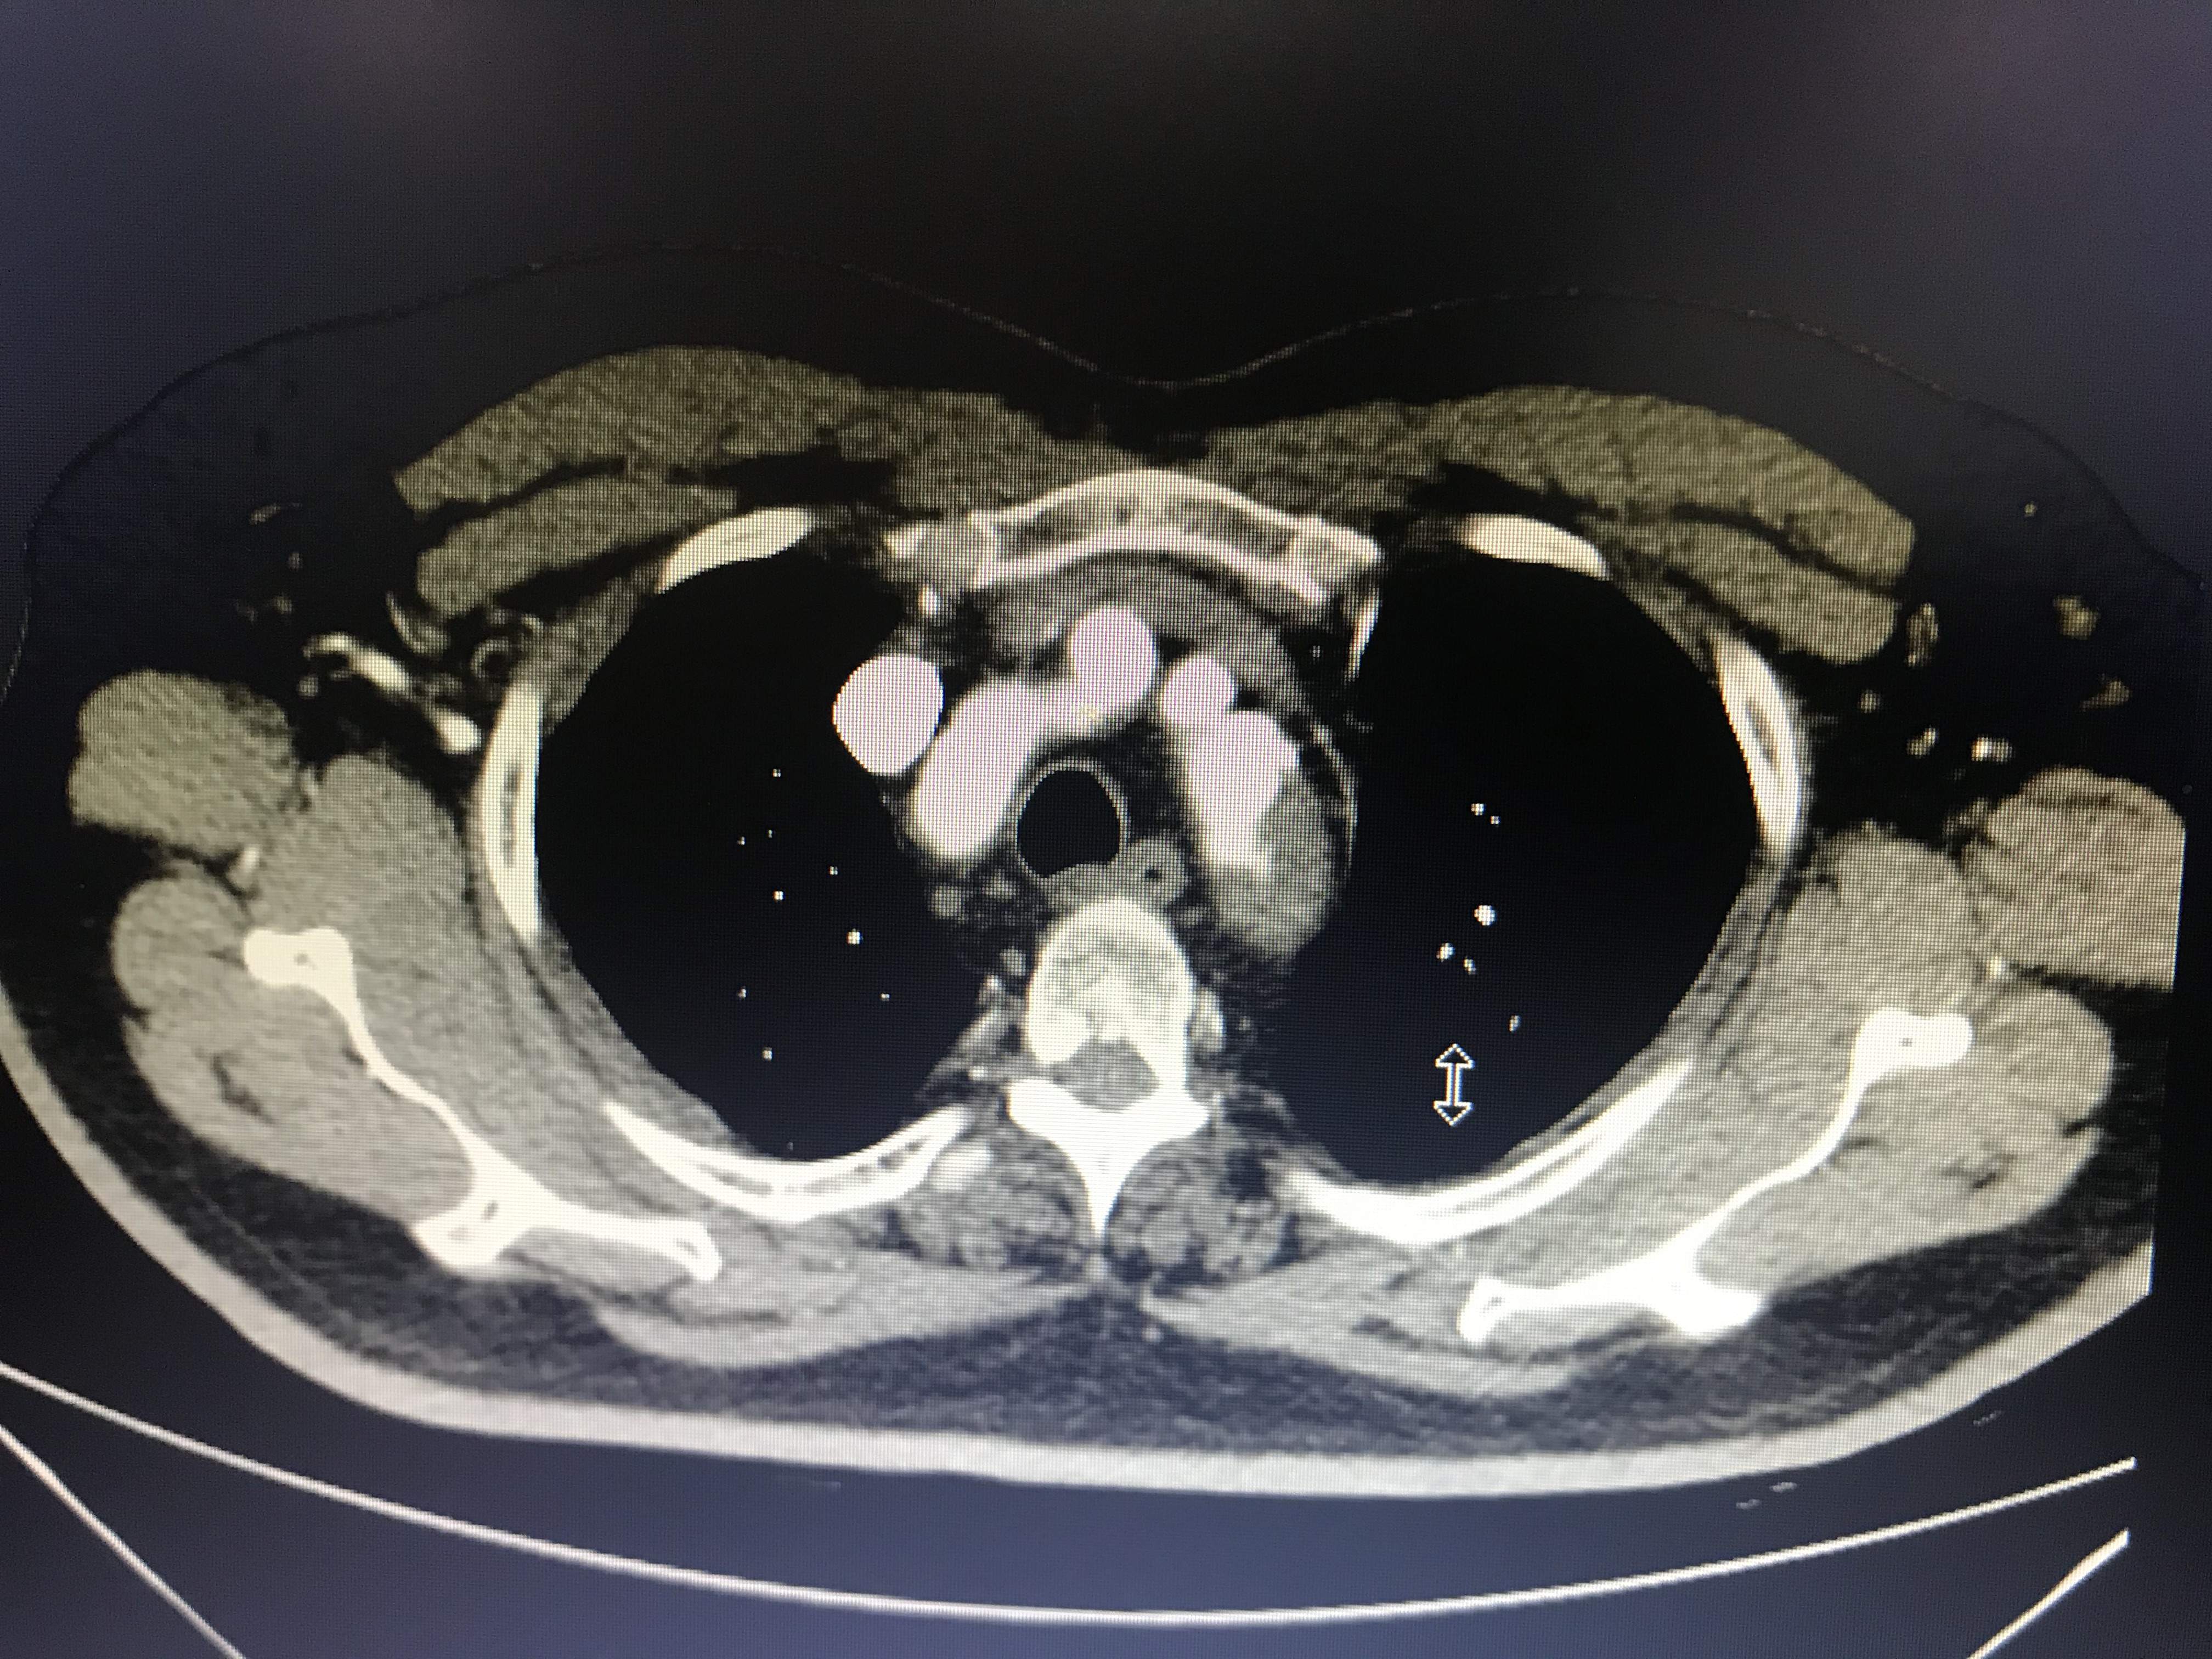

病人胸痛,这图像竟然不是主动脉溃疡?

大家帮我忙看看,到底是不是主动脉溃疡?